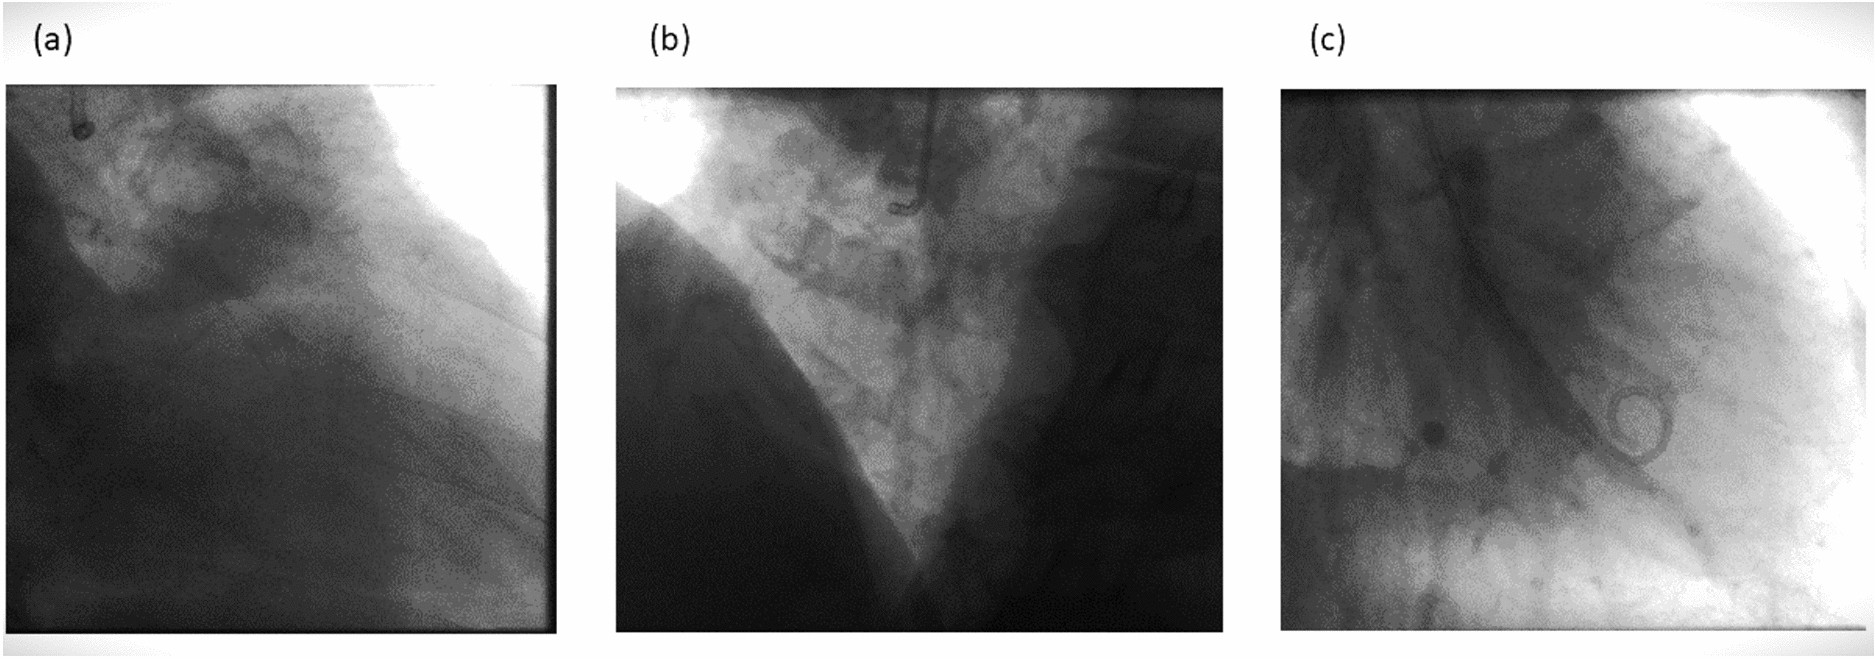

Angiographic frame just before the injection of contrast agent. (a) Angiogram of the left coronary artery (b) Angiogram of right coronary artery (c) Angiogram of the left ventricle.